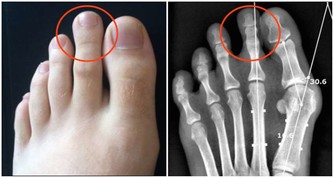

★ 揉大敦穴

大敦穴所處的腳拇趾是肝經的起始處,肝經由此巡行到生殖器、肝、腦、眼等部位,按壓大敦穴可以疏肝理氣,激發人體少陽之氣。

常按此穴,對肝火旺盛引起的目眩、腹痛、肌肋痛等有緩解作用。

取穴方法:可採用正坐或仰臥的姿勢,大敦穴在腳拇趾靠第二腳趾那一側甲根邊緣約2毫米處。